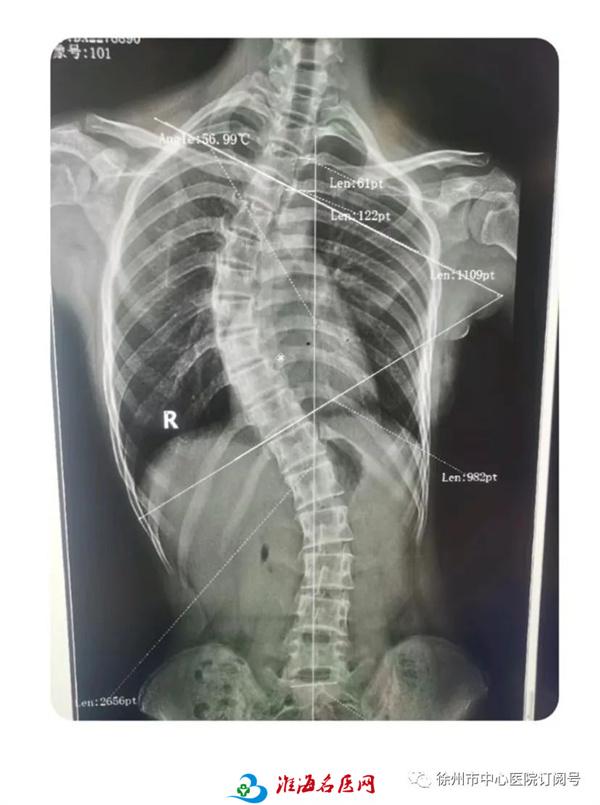

冯杰在结合患者口述病史、查体及影像学检查结果后,认为小文的脊柱侧弯度数符合手术指征,需要进行手术治疗。在麻醉科、手术室团队的通力合作下,冯杰为小文在全麻下成功实施了“脊柱侧弯矫形植骨内固定术”。日前,小文已经顺利出院,她将继续进行康复功能锻炼并进行定期随访复查。

小文术前术后

影像对比

冯杰介绍,“如果脊柱侧弯畸形不是很严重的话,可以通过戴支具,平常注意摆正坐姿进行纠正;但如果像小文一样脊柱侧弯的病情比较严重,就需要进行手术矫正了。”近年来,徐州市中心医院骨科在脊柱畸形诊疗方面已累积大量的临床经验,青少年脊柱侧弯的手术治疗技术方面已发展得十分成熟,实实在在为区域内青少年脊柱侧弯患者带来了便利。